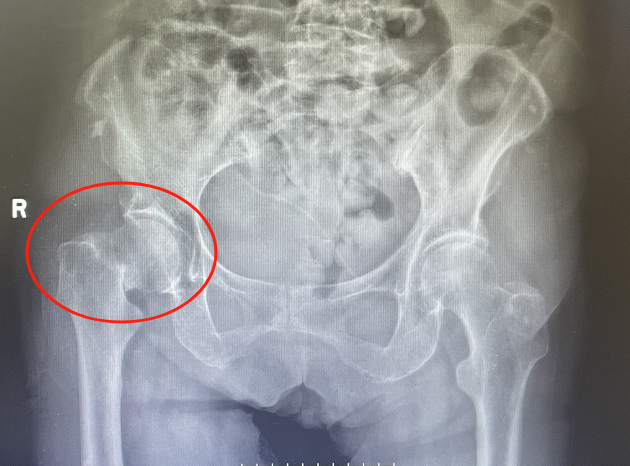

入院后檢查發(fā)現(xiàn)老人右側(cè)股骨頸骨折,更加麻煩的是張奶奶有高血壓病、冠心病、腦梗塞等病史20余年。高齡、基礎(chǔ)疾病多,手術(shù)風(fēng)險(xiǎn)高。但骨折后保守治療,需要長(zhǎng)期臥床,疼痛難忍,吃喝拉撒都要在床上進(jìn)行,并發(fā)癥多,生活質(zhì)量下降?!笆中g(shù)?還是不手術(shù)?”張奶奶的家屬可發(fā)了愁?!白詈玫姆椒ㄟ€是控制內(nèi)科疾病后,幫忙老人盡早手術(shù)治療吧!”經(jīng)過骨科副主任醫(yī)師徐光輝耐心與家屬溝通后,家屬要求積極手術(shù)治療。

手術(shù)當(dāng)日,在麻醉科、內(nèi)科、骨科醫(yī)療團(tuán)隊(duì)的共同努力下,陳上衛(wèi)、徐光輝醫(yī)師團(tuán)隊(duì)為張奶奶行右側(cè)人工股骨頭置換術(shù),術(shù)中嚴(yán)密監(jiān)測(cè)血壓減少術(shù)中出血量。手術(shù)歷時(shí)40分鐘,順利完成。術(shù)后復(fù)查X光片,人工髖關(guān)節(jié)位置良好,術(shù)后第一天即可下床站立,并在助行器輔助下行走??祻?fù)科孫秀珍副主任醫(yī)師為張奶奶制定術(shù)后康復(fù)方案,在出院前,再次告知術(shù)后康復(fù)的重要性,以及預(yù)防再次跌倒的措施。